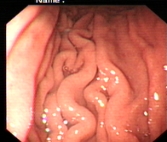

正常胃表现